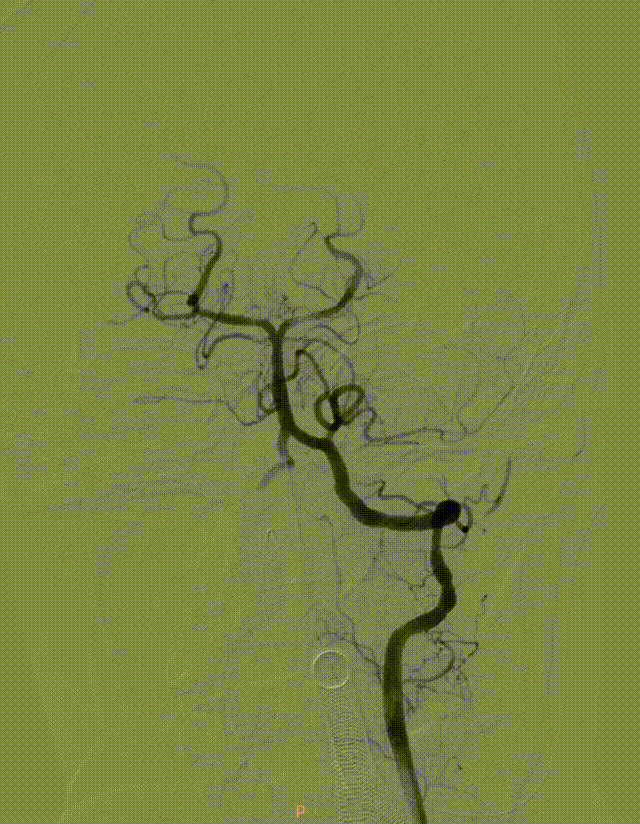

左侧椎动脉造影。

6F 125cm 通桥银蛇®颅内支持导管到位。

6F 125cm 通桥银蛇®颅内支持导管抽吸过程。

负压抽吸2次,基底动脉顶端部分再通,见栓子向双侧大脑后动脉逃逸。

微导丝携带微导管至右侧大脑后动脉P3段,抽拉结合取栓一次见右侧大脑后动脉再通。

微导丝携带微导管至左侧大脑后动脉P3段,抽拉结合取栓一次见左侧大脑后动脉再通。

左侧大脑后动脉P1段发白,观察20min较前好转,血流状态维持良好,结束手术。